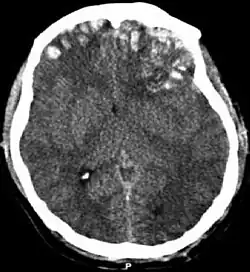

| CT scan showing cerebral contusions, hemorrhage within the hemispheres, and subdural hematoma. There is also displaced skull fracture of left transverse parietal and temporal bones.[2] | |